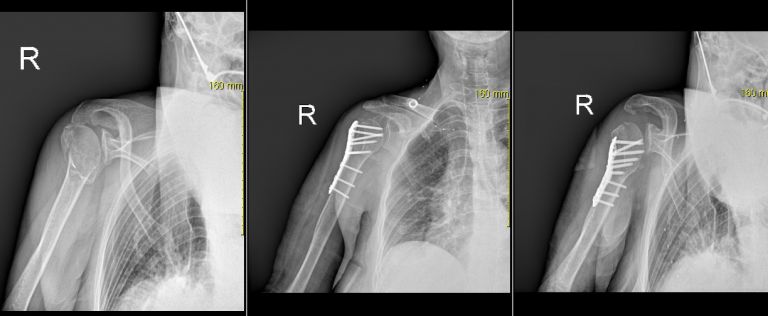

하지

하지-2